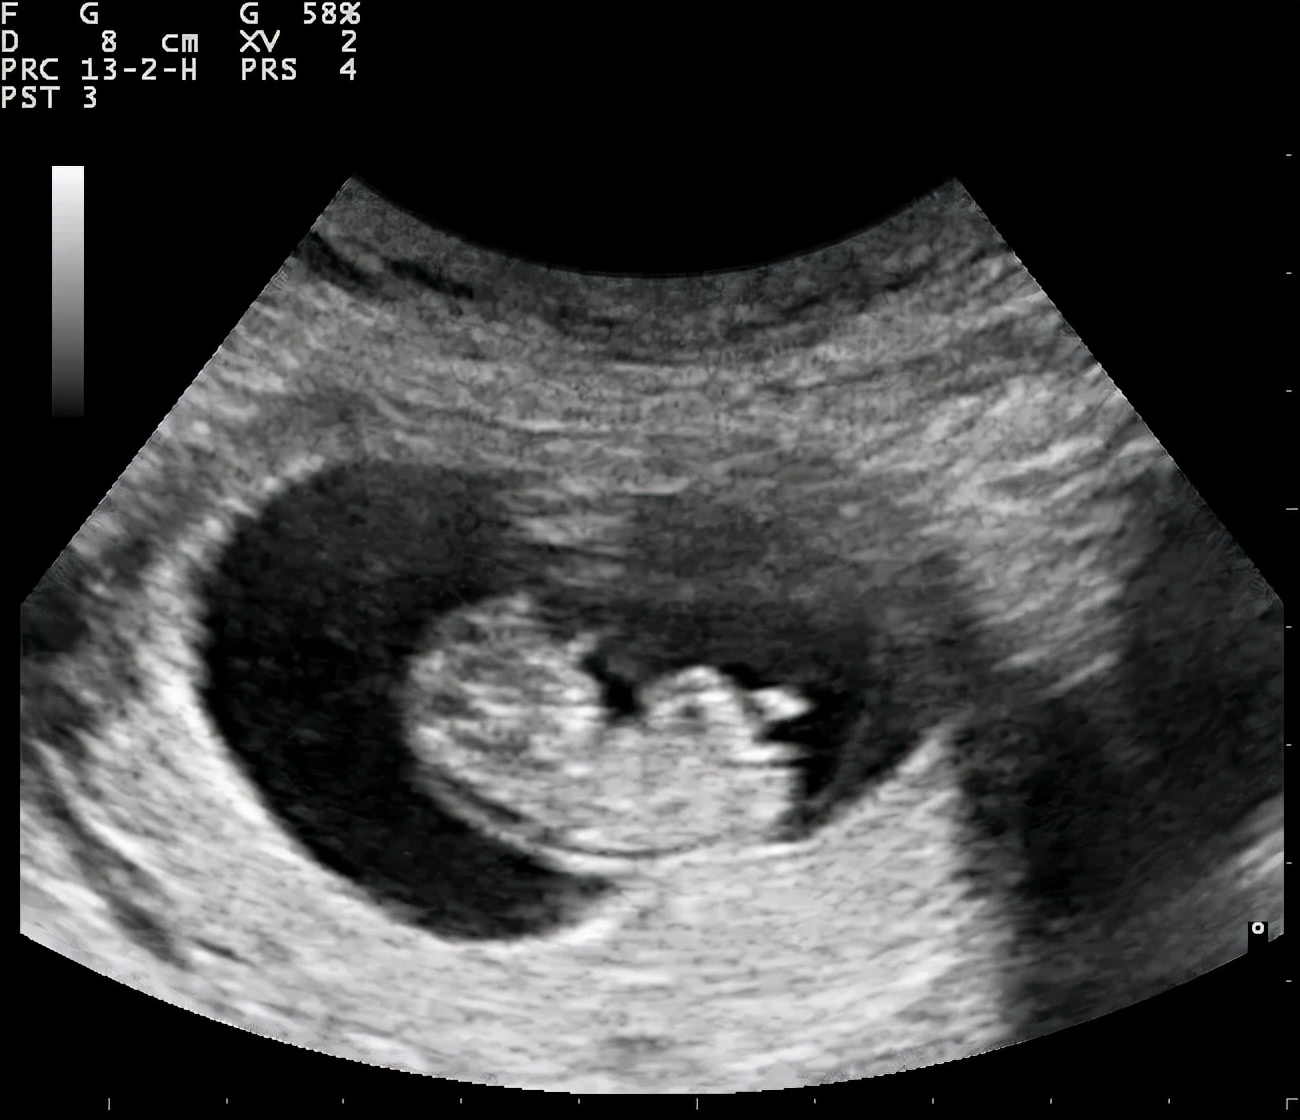

超声图像显示的早期胎儿 | 图源:Wikimeidia Commons

这种凝胶的正式名称是超声耦合剂,它的主要用途正如它的名字,是用来“耦合”的媒介。超声检查用人耳听不到的超声波(频率大于20千赫)扫描人体,并把回声信号转换成体内的图像信息。B超呈现的是不同亮度 (Brightness)的黑白图像,而彩超则是在此基础上以彩色呈现组织的血流情况。